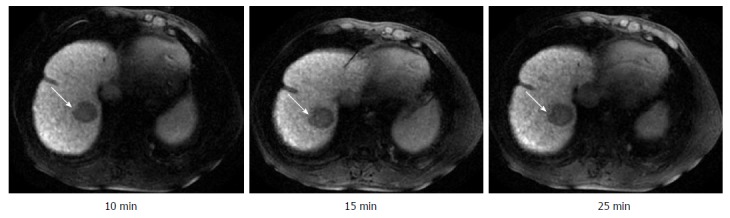

Figure 3.

Visibility of a hepatocellular carcinoma focus at different hepatobiliary phase delay time points in a patient with Child-Pugh A cirrhosis. An HCC focus of 0.8 cm × 0.8 cm was found in the right rear lobe of the liver in a 53-year-old female patient with cirrhosis caused by chronic hepatitis B. Gd-EOB-DTPA-enhanced magnetic resonance imaging shows a strong contrast between liver parenchyma and HCC focus presenting as obvious hypointensity (+++). The contrast at DT-10 is enough to identify the HCC focus. HCC: Hepatocellular carcinoma.